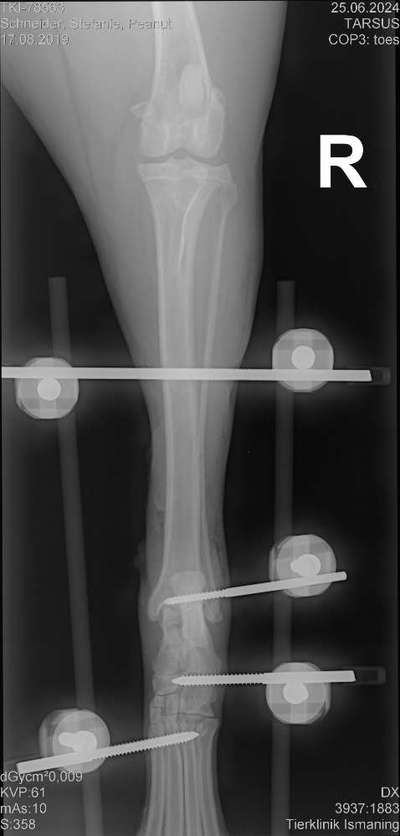

Hallo zusammen, mein 5 jähriger Rüde wurde am Dienstag wegen seiner gerissenen Achillissehne operiert. Ich suche nach Beschäftigungmöglichkeiten die im Liegen stattfinden können. Außerdem würde ich mich freuen um eine PN, wenn ihr auch einen Hund habt der sich die Achillissehne schonmal gerissen hat. Lg Steffi